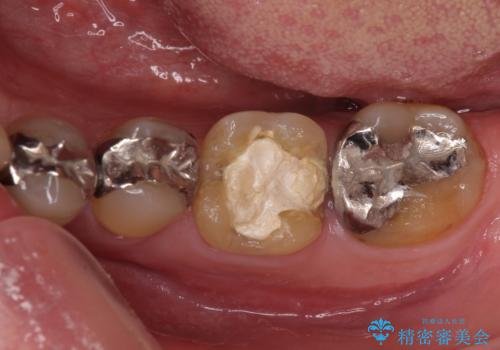

- 歯肉が退縮したためにクラウンの縁や歯根が見えてしまっていることを気にして来院された患者様です。

仮歯に変えた後にオールセラミッククラウンにて補綴することとしました。

強い咬合力や磨きすぎなどにより、歯根が見えてしまったり、金属の縁が見えてしまったりし、審美障害を引き起こすことがあります。